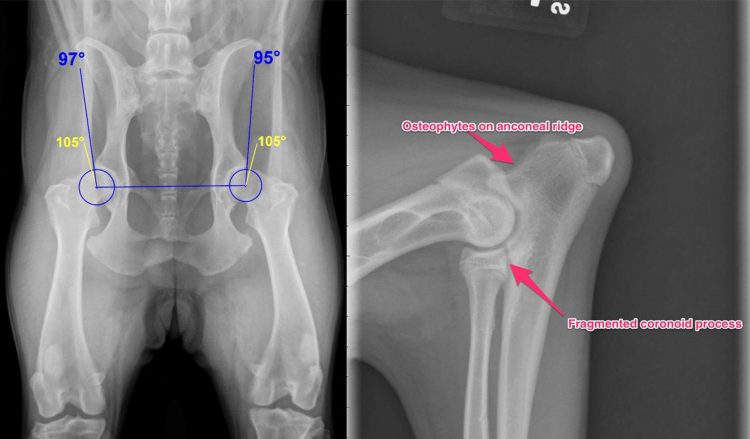

Displazia de sold la caine